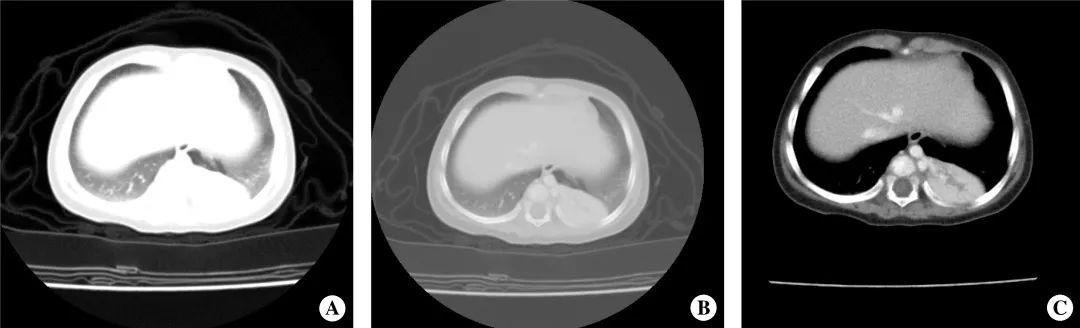

图34-5 左下肺隔离症

女,8 个月,左肺下叶邻近脊柱旁可见软组织影,边界清楚,增强扫描血供丰富,明显不均匀性强化,其内可见来自主动脉供血血管。

A. 肺窗;B. 胸双窗;C. 纵隔窗增强